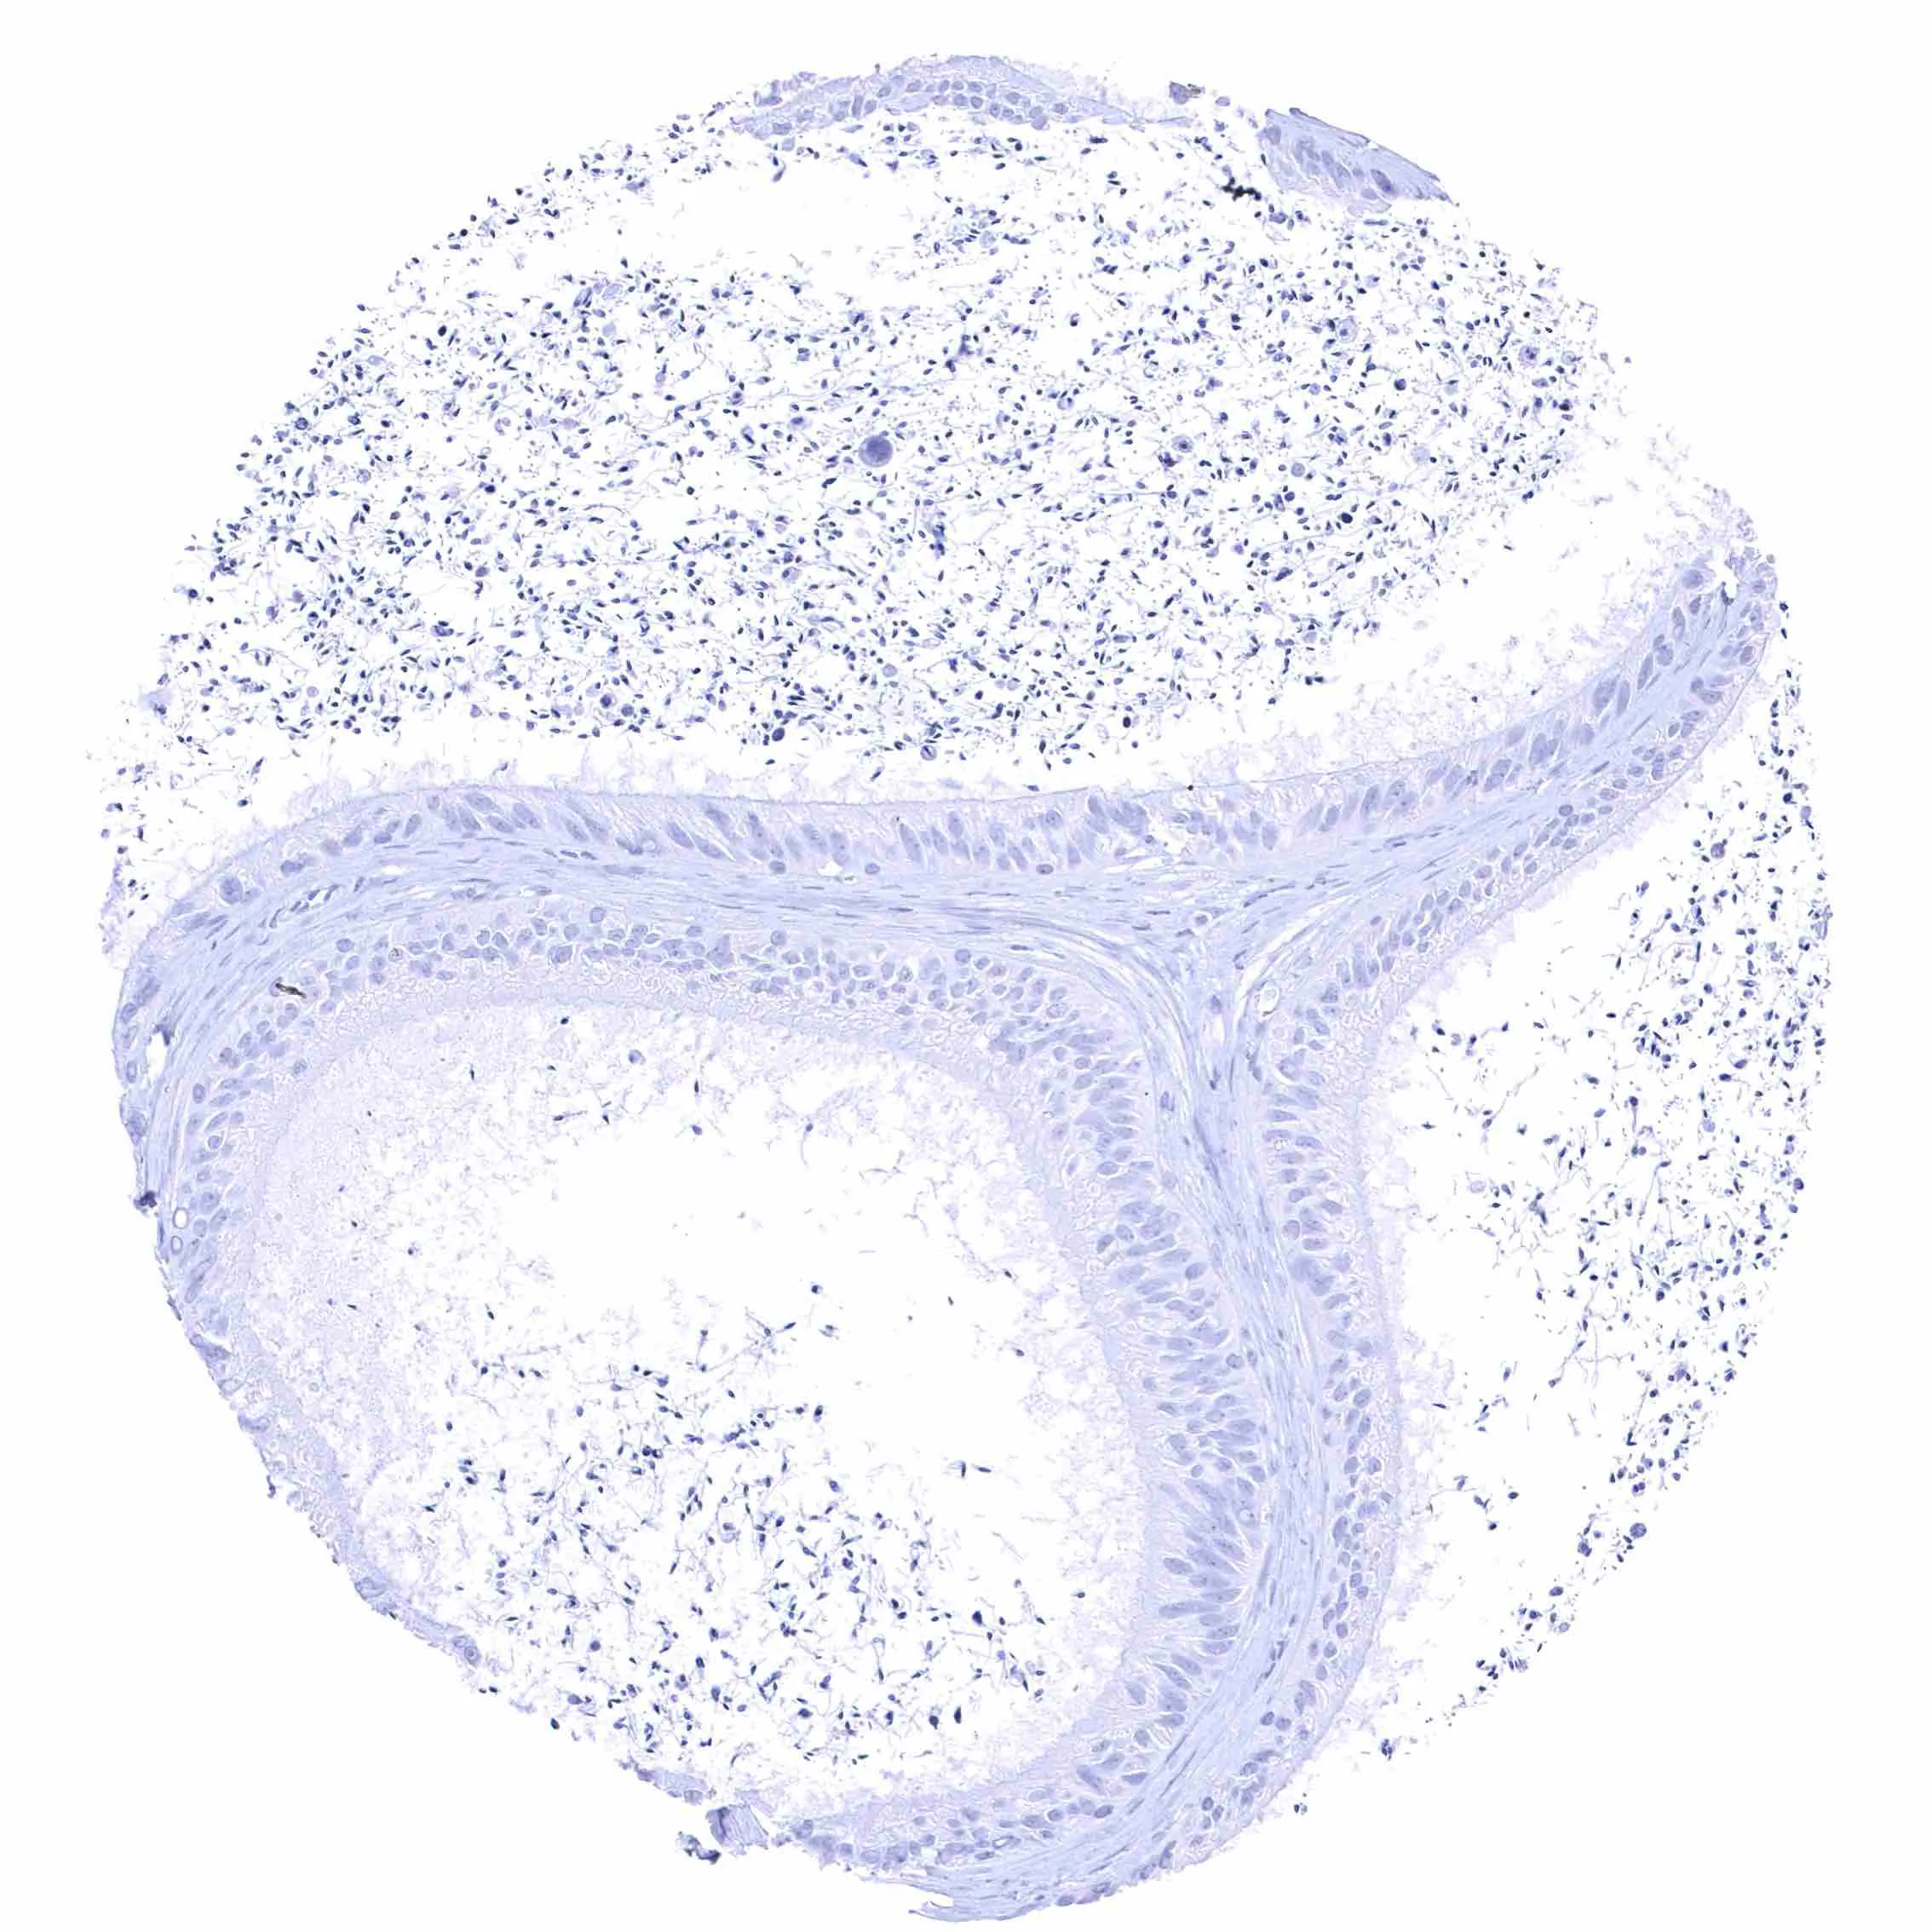

Uterus, ectocervix

Uterus, endocervix